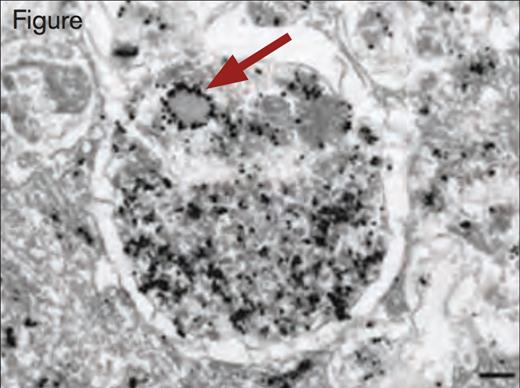

Immunogold Detection of vWF Protein in a Weibel–Palade Body Within an Autophagosome. Scale bar, 200 nm. Reprinted by permission from Macmillan Publishers Ltd: Nature Medicine. 2013; 19(10):1282, Copyright 2013.

By use of immunoelectron and immunofluorescence microscopy, the authors observed that Weibel–Palade bodies and autophagosomes are located in cultured human umbilical vein endothelial cells (HUVECs) in closer proximity than expected by chance. Additionally, they observed that Weibel–Palade bodies and autophagosomes are occasionally found fused together. Additional immunoelectron microscopy using anti-vWF antibodies revealed the presence of vWF in autophagosomes. Lentiviral shRNA-mediated knockdown of the autophagy genes, Atg7 and Atg5, in HUVECs produced several abnormalities on vWF expression. Although the intracellular concentration of vWF was not reduced, the ratio of pro-vWF to mature vWF was significantly increased in Atg7 or Atg5 knockdown cells. Stimulated release of vWF by histamine or vascular endothelial growth factor was reduced. Two inhibitors of autophagosome function, chloroquine and bafilomycin, blocked stimulated release of vWF from HUVECs. Additionally, the number and size of Weibel–Palade bodies was decreased in Atg7 and Atg5 knockdown cells, as well as in cells treated with chloroquine or bafilomycin. The rate of exocytosis of Weibel– Palade from endothelial cells was also decreased in Atg7 knockdown cells compared with normal HUVECs.